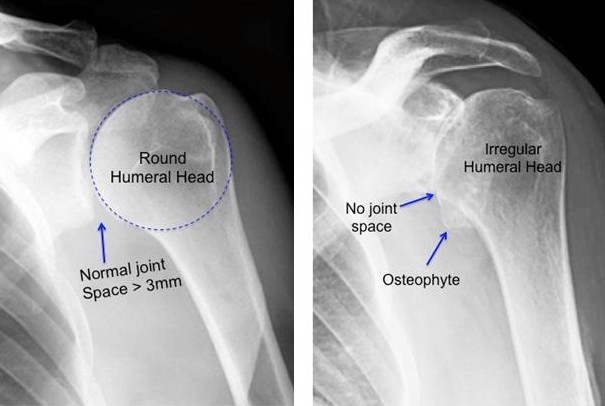

With old age the Articular Cartilage wears off, a condition referred to as “wear and tear.” That is when most people begin to feel symptoms of pain or stiffness in the upper arm. The head of the humerus experiences severe pain through the overuse of the cartilage leading to arthritis. The damaged cartilage of the glenohemural joint (Shoulder joint) decreases the space between the head of the humerus and the socket of the scapula. Causing the bones to rub against each other during motion. This condition is called Osteoarthritis, which occurs in people over 65 or with a family heritage of arthritis. As a result of the cartilage decaying, bone on bone friction takes place, causing stiffness and limited mobility.

Note the differences in space between the humerus and the scapula in the figures below. On the left is a healthy shoulder joint with normal space between the two bones. While the X-ray on the right shows little to no space in between the bones. As the cartilage that covers the ends of the bones wears away, it can result in bone rubbing on bone and produce painful bone spurs.